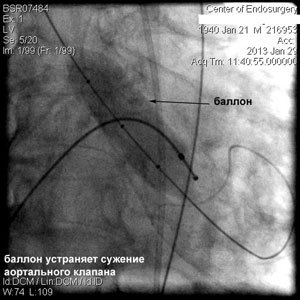

Через прокол (или маленький разрез) в артерии, в сжатом состоянии проводят искусственный клапан, который расширяется при его установке на месте поврежденного аортального клапана. После раскрытия клапан начинает функционировать и восстанавливает полноценную и нормальную работу аорты.